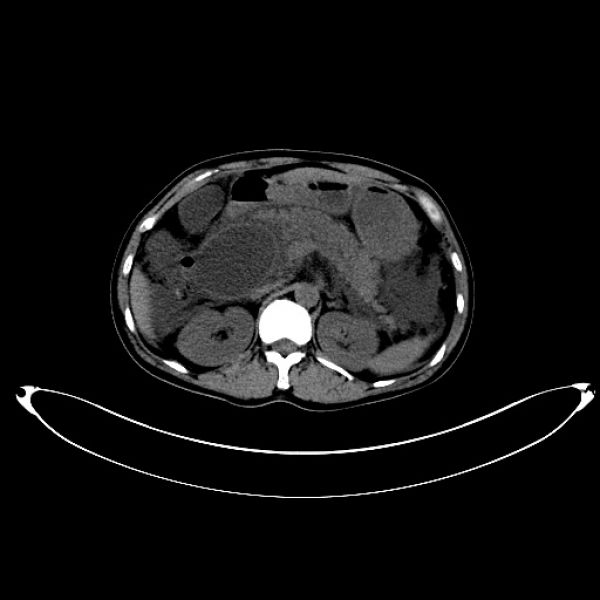

石某某,因突发上腹痛疼痛10小时入院。入院时完善急诊血常规、生化、肝功能、胰代谢以及肝胆脾增强CT等检查,考虑诊断“急性胰腺炎;胰腺假性囊肿”,进一步完善磁共振平扫+MRCP检查,确诊为胆总管囊状扩张症(Ia、C-P型)并发急性胰腺炎。首先进行胰腺炎治疗,予以禁食禁饮、抗炎、护胃、补液、抑制胰腺内外分泌、通便等治疗。经积极治疗,病情稳定后,复查生化相关指标恢复正常,王文儿主任指示:完善术前相关评估,有限期手术指征,无明显手术禁忌,于4月16日在麻醉科及护理工作人员的积极配合下成功完成全腹腔镜下胆总管囊肿剥除+胆囊切除+胆肠内引流术,术中于胆肠吻合口后方放置一18#引流管,术中生命体征平稳,术中失血量约50ml,手术历时约4.5小时,麻醉复苏成功后安返病房。

在诊疗过程中科学的诊疗决策对于患者诊治过程中的顺利推进起到举足轻重的作用。患者因上腹痛10小时入院,完善相关生化以及CT影像检查发现:第一,胰代谢异常明显,结合临床表现和影像学检查,急性胰腺炎诊断明确;第二,上腹部CT发现胰头区有囊性占位,报告:假性囊肿形成可能。王文儿主任仔细阅片以及根据发病特点分析,胰头区囊性占位极似胰腺假性囊肿,根据腹痛特点及胰代谢指标分析,最容易考虑诊断为“急性胰腺炎并假性囊肿形成”。但是,王文儿主任进一步指出:发病时间短,一般不可能在短时间内形成假性囊肿,那么就应该考虑是否还有其他病变?是否考虑胆总管囊状扩张症?那么,就需要进一步完善检查,诊断胆总管囊状扩张症最有价值的方法就是MRCP,于是完善MRCP检查后证实了王文儿主任的推断,最终患者诊断为胆总管囊状扩张症(C-P型)并急性胰腺炎。最后我们的诊疗方案分两步走:第一,积极治疗并发症。第二,待病情稳定后实施腹腔镜胆总管囊肿剥除+胆囊切除+胆肠内引流,以加速康复理念为指导,实现患者快速康复出院,赢得病人的信任。

术前影像图片